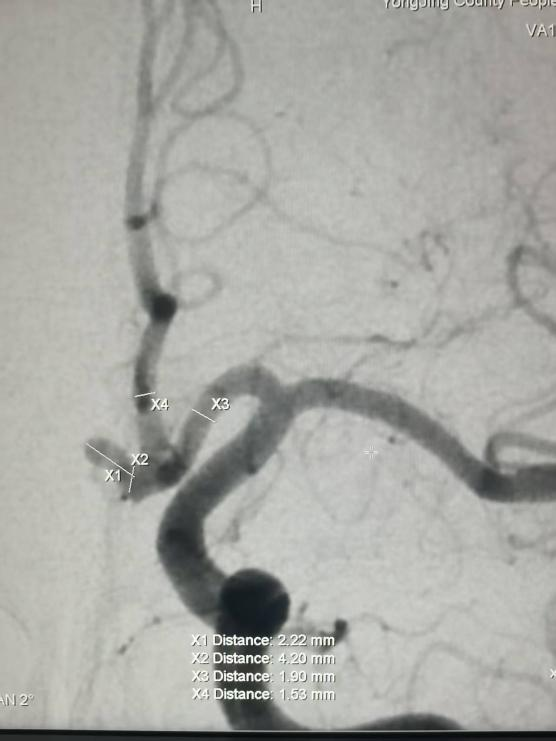

手术台上,无影灯下,一场精细的“生命保卫战”悄然打响。滕宏涛主任带领帮扶专家孔令超医师及党文平主任,为患者成功实施了“支架辅助下颅内动脉瘤介入栓塞术”。这是一项技术要求极高的微创手术,如同在错综复杂的血管迷宫中,为脆弱的动脉瘤壁精准地放置一个“保护支架”,再用比头发丝还细的微导管将栓塞材料填入瘤体,彻底解除破裂风险。

步骤精准无误,操作沉稳娴熟。最终这颗“颅内炸弹”被成功拆除。这是永靖县人民医院首例神经血管介入手术,标志着该院在脑血管疾病介入治疗领域实现了“零的突破”。